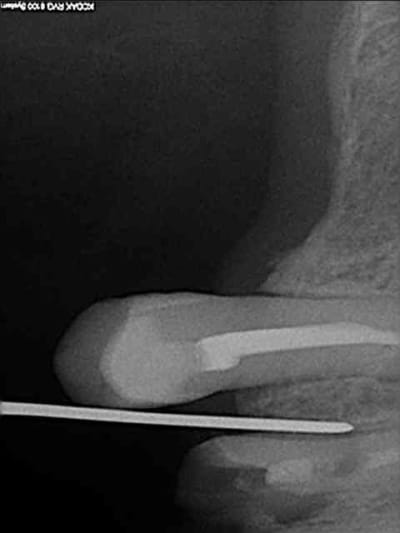

18/10/2011 à 11h19

aussitôt demandé, aussitôt fait !!

(j+1 an)

tu as perdu pas mal d'os!!